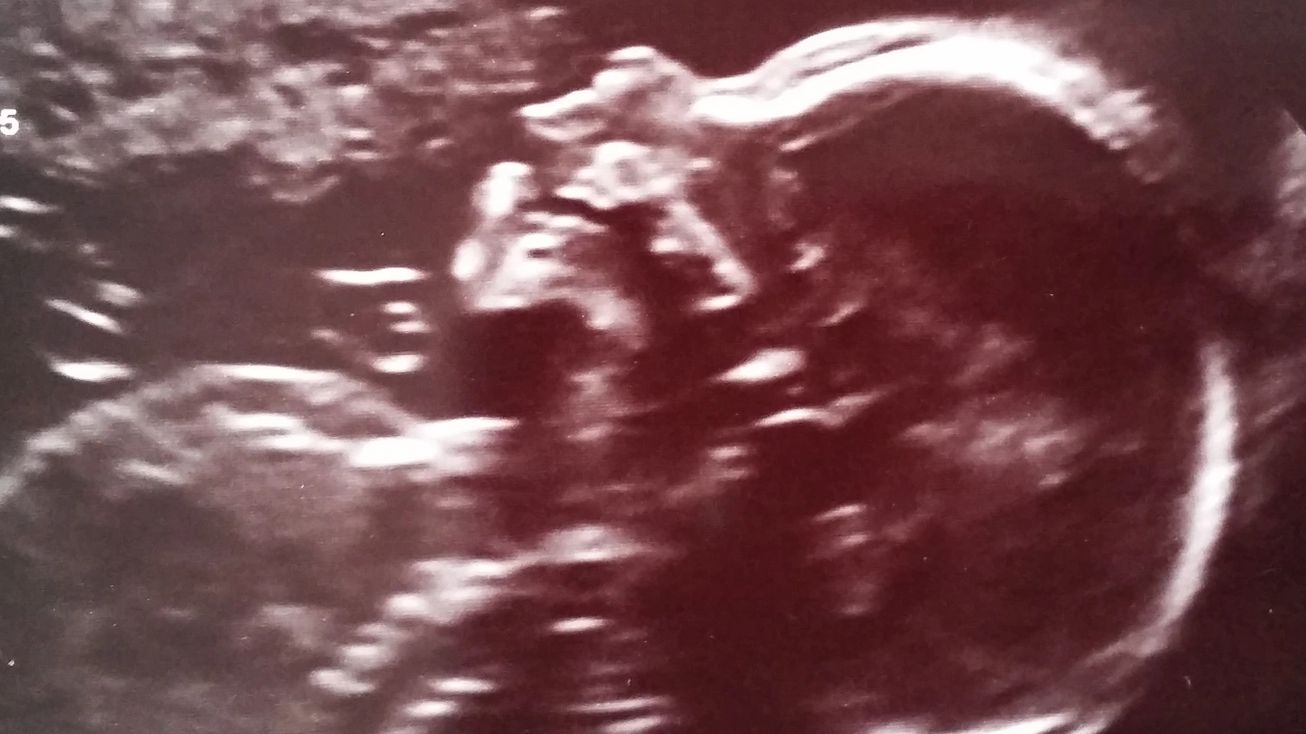

Das Zwerchfell entwickelt sich ca. in der 8 -10 SSW. Kommt es hier zu einer Störung, kann sich eine Lücke bilden. Es ist ca. ab der 18.SSW möglich, die angeborene Zwerchfellhernie bereits vor der Geburt (pränatal) mit einer Ultraschalluntersuchung zu erkennen. Die vorgeburtliche Entdeckung einer Zwerchfellhernie ist jedoch gar nicht so leicht, und daher ist es wichtig, dass der Gynäkologe die Ultraschalluntersuchung gründlich und aufmerksam durchführt.

Bei linksseitigen Hernien ist die Entdeckung ein wenig leichter, da die Verlagerung des mit Fruchtwasser gefüllten und daher auf dem Ultraschallbild schwarz erscheinenden Magens in den Brustraum (Thorax) sowie die Verdrängung des Herzens nach rechts sofort ins Auge fallen.

Bei rechtsseitigen Defekten ist die Diagnose weitaus schwieriger, da das Herz in diesem Fall nach links verlagert erscheint und die in den Thorax verschobenen Organe, insbesondere die Leber, ähnlich aussehen wie die noch nicht entfalteten Lungenflügel und deshalb kaum von ihnen unterschieden werden können.

Besteht der Verdacht, dass eine angeborene Zwerchfellhernie vorliegt, empfiehlt es sich in jedem Fall, zur weiteren Abklärung eine Feinultraschalluntersuchung und eine Magnetresonanztomographie (MRT) durchführen zu lassen.